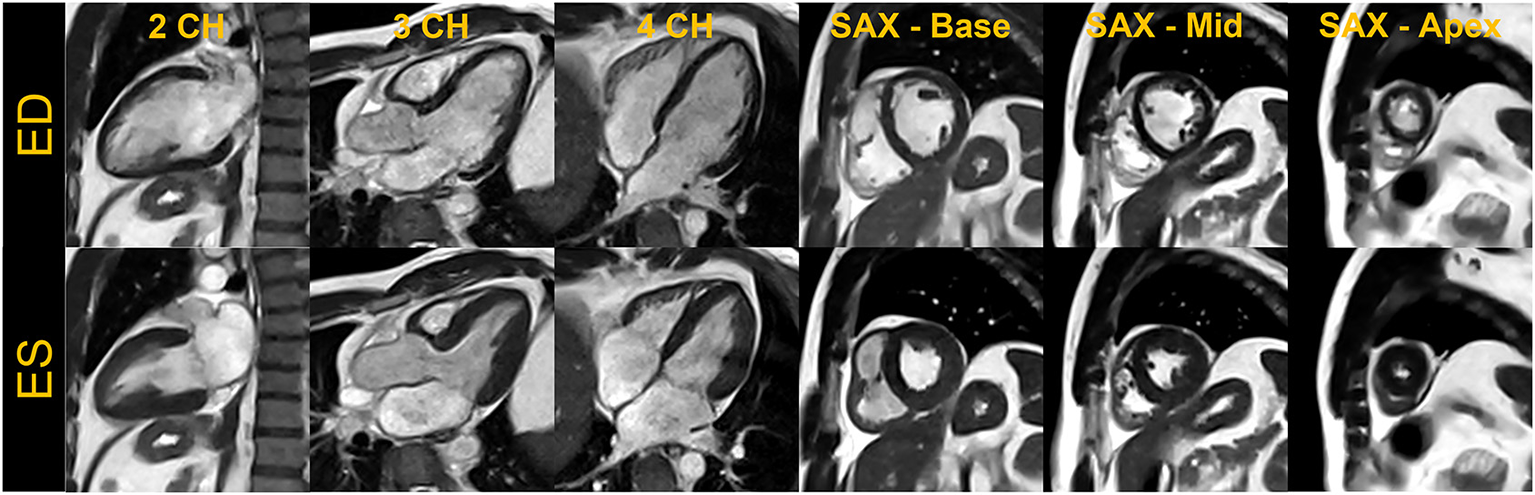

For breath-held segmented bSSFP cine, a CS-accelerated sequence with a variable density sampling k-space pattern and Cartesian readout was utilized. Figure 2 shows representative end-diastole and end-systole images from a volunteer in standard cardiac views. The acquired spatial resolution was set to match protocols on our clinical 1.5 T and 3 T systems (MAGNETOM Vida, Siemens Healthcare, Erlangen, Germany). The acceleration rate was adapted based on the subject's R-R interval (a typical rate was 4.3) to maintain a temporal resolution of ~30 ms, meeting recommendations of the SCMR (11). The number of iterations and the regularization parameters for the CS reconstruction were determined based on informal visual perception of image quality, signal-to-noise, and artifact. Asymmetric sampling was utilized to minimize TE and TR for the cine; however, limited gradient slew rate prolonged the TE and TR on the 0.55 T system when compared to 1.5 T. Specific Absorption Rate (SAR) scales with the square of the field strength; therefore, higher flip angles of 90° to 110° were possible for bSSFP cine at 0.55 T (8) as compared to 1.5 T or 3 T, where maximum flip angles are in the range of 50° (3 T) to 80° (1.5 T). A flip angle in the range of 110° has previously been shown to maximize blood-myocardium contrast in bSSFP (8). While our clinical protocols at 1.5 T and 3 T using the same sequence are set to a three-shot acquisition requiring three heartbeats (HB) per slice, at 0.55 T, the acquisition time was increased to six heart beats per slice to meet spatial and temporal resolution requirements, without pushing the acceleration rate too far. On the other hand, a segmented GeneRalized Autocalibrating Partial Parallel Acquisition (GRAPPA) bSSFP cine with rate 2 acceleration, 24 separate reference lines, and similar acquisition parameters required 10 HB per slice at 0.55 T (Figures 1, 3) when compared to the CS implementation.

End-diastole (ED) and end-systole (ES) cardiac frames from a compressed sensing-based breath-held segmented balanced steady-state free precession cine. Images acquired from a single volunteer are shown in standard cardiac views– two-chamber (2CH), three-chamber (3CH), four-chamber (4CH) and base, mid, and apical slices in short-axis (SAX).